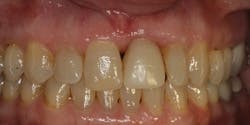

Fig. 4 One week postop

We immediately took the crown out of occlusion in both centric and protrusive movements. Using the Biolase Waterlase laser with the radial fire perio tip, we completed gingival surgery, including mechanical debridement. This surgery was accomplished without a flap or sutures. The patient was also placed on antibiotics. One week later the patient returned with the area looking and feeling better. (Fig. 4)